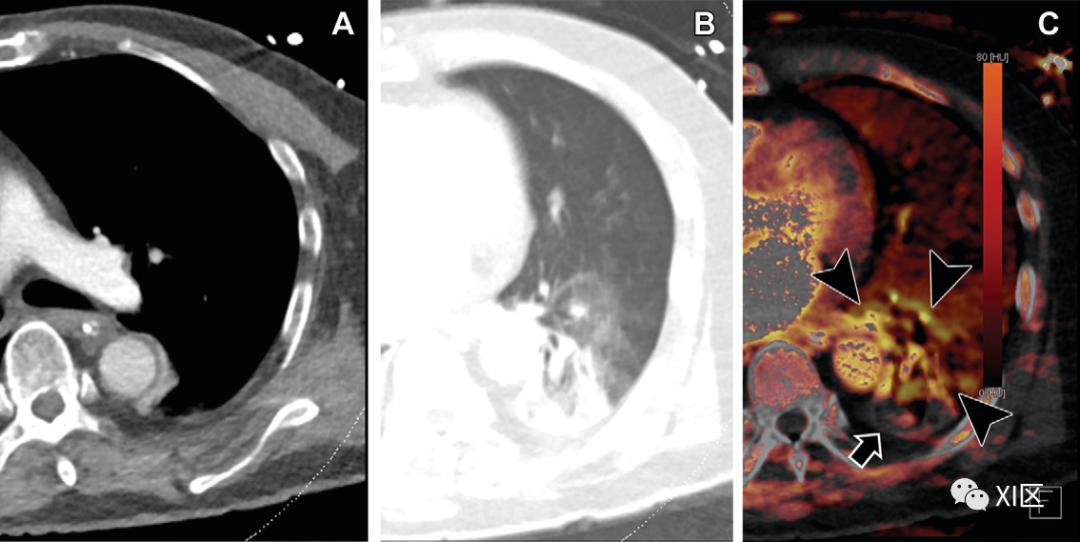

新冠肺炎双能CT经常报告肺灌注异常(图10)。异常灌注表现为各种形状,包括楔形、斑点或混合模式,以及各种灌注模式,包括与肺阴影区域相对应的缺血和阴影周围充血。新冠肺炎的这种异常灌注通常伴随着近端和远端肺血管充血,主要是在肺阴影区域内或周围,推测是由于生理性缺氧性肺血管收缩失败所致。肺灌注异常与肺栓塞和气道异常明显,假设的原因也是缺氧性血管收缩、微血栓或毛细血管减少。临床上,肺灌注异常与通气灌注不匹配和缺氧有关。

图10:新冠肺炎患者的肺灌注异常。(A,B)一名83岁男性确诊为新冠肺炎患者的轴位增强双能灌注CT图像显示,周围分布着磨玻璃样变和双侧肺下叶实变,没有肺血栓栓塞的证据。(C) 灌注图显示病变周围充血(箭头)和病变缺血(箭)。彩色条显示肺部灌注程度;深色和亮色分别表示低灌注和高灌注。新冠肺炎的气道损伤